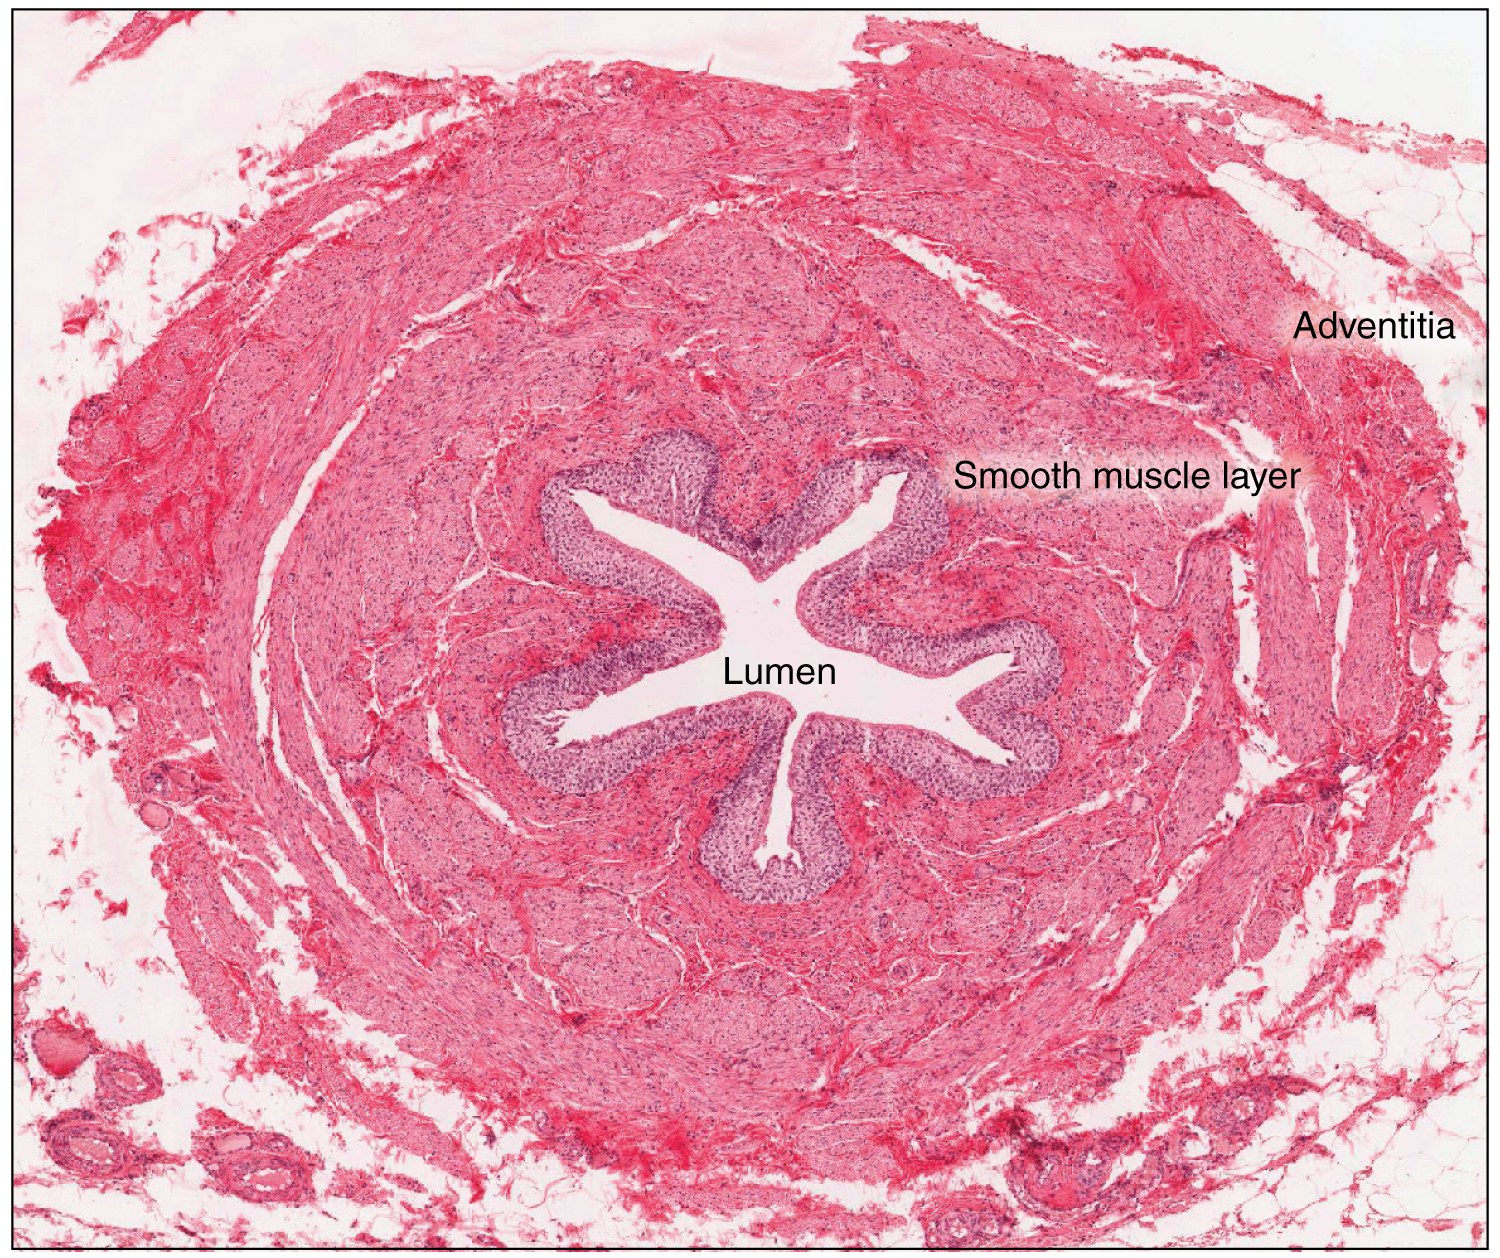

수뇨관은 팽창에 반응하는 이행 상피의 일종인 요로 상피로 덮여 있다. 이행 상피는 이완 시 원주 상피 세포층으로, 팽창 시 편평 상피 세포로 나타난다. 상피 아래에는 고유층이 있는데, 혈관, 정맥, 림프관이 산재한 탄성 섬유가 많은 느슨한 결합 조직이다. 수뇨관은 내측 종주 근육층과 외측 환상 또는 나선형 근육층의 두 근육층으로 둘러싸여 있다.[5][6] 수뇨관 하부 1/3에는 세 번째 근육층이 있다.[6] 이 층 바깥쪽에는 혈관, 림프관, 정맥을 포함하는 모험막이 있다.[6]